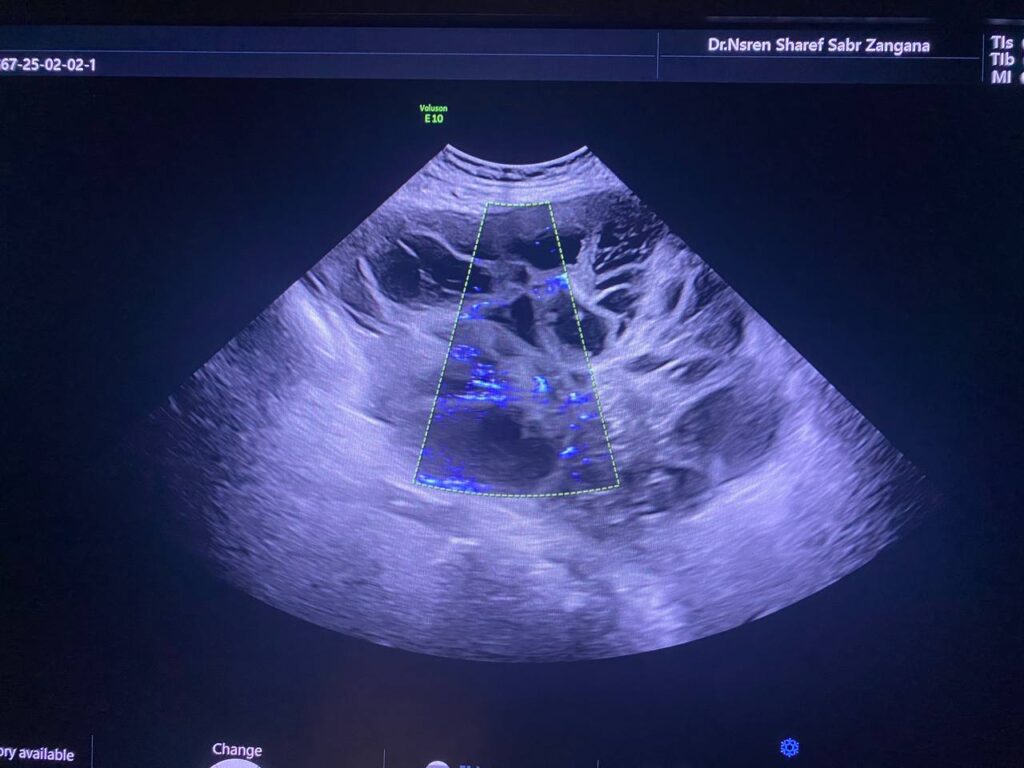

Right ovarian multilocular (>60 locules) solid mass , its size 170x140mm vascular on color doppler , color score 3-4 , with indistinct margins , associated with ascites , contains fine echoes , picture mostly of primary ovarian cancer ORADS 4 , no mass seen in the left ovary